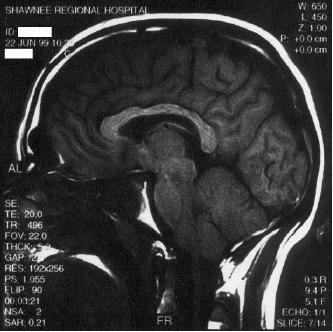

Doctor: This is your brainI've seen my own brain. (I had an MRI years ago, in an attempt to diagnose my migraine headaches.)

I even have a .PNG of it.

I've seen my own brain. (I had an MRI years ago, in an attempt to diagnose my migraine headaches.)

Doctor: This is your brain

Clever: And now you're going to show me my brain on drugs right?

Doctor: No, why would I?